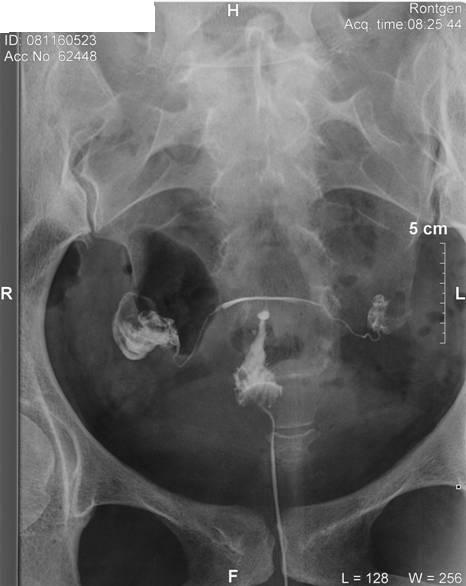

Hát hsg megvolt, nem volt egy rózsaszín leányálom mire felrakta a katéter, mert csak a második katéter ment be a helyére, és sokadik próbálkozásra!!!! :cry: Nem kívánom senkinek!!!!! De túl vagyok rajta, jobb mint a lapar!!!!!! :roll:

Szóval a helyzet az, hogy történt valami odabent, mert rettentő vékonyak lettek a vezetékek, kanyargósak, és a főnököm és az itteni nőgyógyi (aki felrakta a katétert) szerint hegesen gyógyultam régebbi gyulladásból. :cry: Szerinte ne is az inszemivel, hanem a lombikkal próbálkozzunk!!!!! :? :cry: Hát elkenődtem, mert nem erre számítottam, hiszen volt laparom, hsg-m eddig teljesen jó eredménnyel. :( Viszont megyek vissza a dokimhoz majd ha megjön, és megmondja a frankót!!!!! Hát ő azért már több ilyet látott, mint ez a nődoki!!!! :shock:

És a képes bizonyíték!!!!

Kép

én sem tudom, mit kell nézni a fotokon. de én is arra gondoltam, hogy ha kanyargos a petevezetö, akkor ott elakadhat a magzat, emiatt biztonságosabb lenne a lombik. ha babás leszel spontán, neked nem árt meg a röntgensugár? vagy nem közvetlen a sugárban dolghozol???